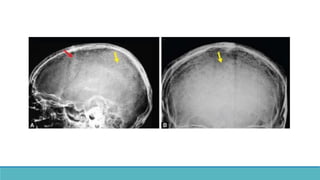

➢Osteoclastic resorption  Cystic lesion in bone.

➢Cavities filled with fibrous tissue and osteoclasts, fibrous

tissue, necrotic and hemorrhagic liquefaction.

➢On x rays : Low density multiloculated cysts

Expansion of bones.

➢ Can be mistaken for neoplastic lesions.

➢Osteoclastic resorption Cystic lesion in bone. ➢Cavities filled with fibrous tissue and osteoclasts, fibrous tissue, necrotic and hemorrhagic liquefaction. ➢On x rays : Low density multiloculated cysts Expansion of bones. ➢ Can be mistaken for neoplastic lesions.